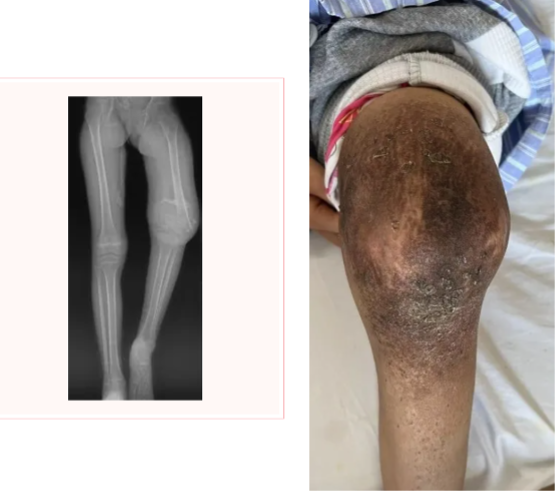

这是一位来自新疆维吾尔自治区的母亲的求助。年仅8岁的麦麦提是一位罹患骨肉瘤的患儿,而更加不幸的是当地确诊时已经出现了病理性骨折。在接受术前化疗后,制定下一步手术方案时遇到了难题。